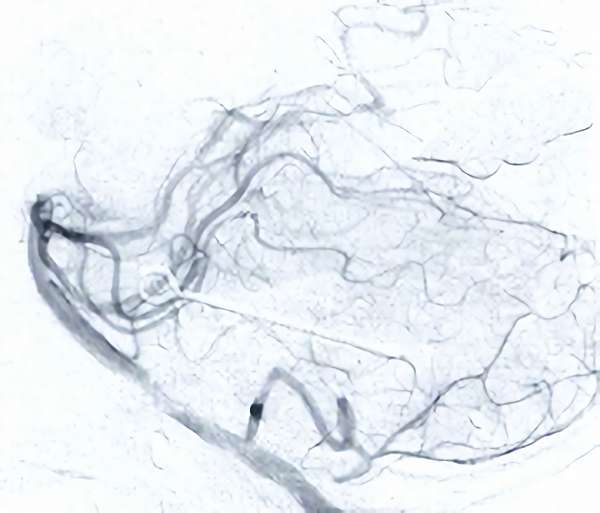

'19年5月

30代

富永/久貝

右中小脳脚 出血再発

SM 3(S1,E1,V1)

米国の病院

No.359 モニタリング

No.359 手術前

No.359 手術中

No.359 手術後

出血既往があり。2回の手術前血管内手術の後に、

Lateral transpeduncular approachにより再々出血予防を目的に

摘出手術を行う。完全摘出であることを確認した。

手術による合併症や後遺症なしで退院した。経過良好。